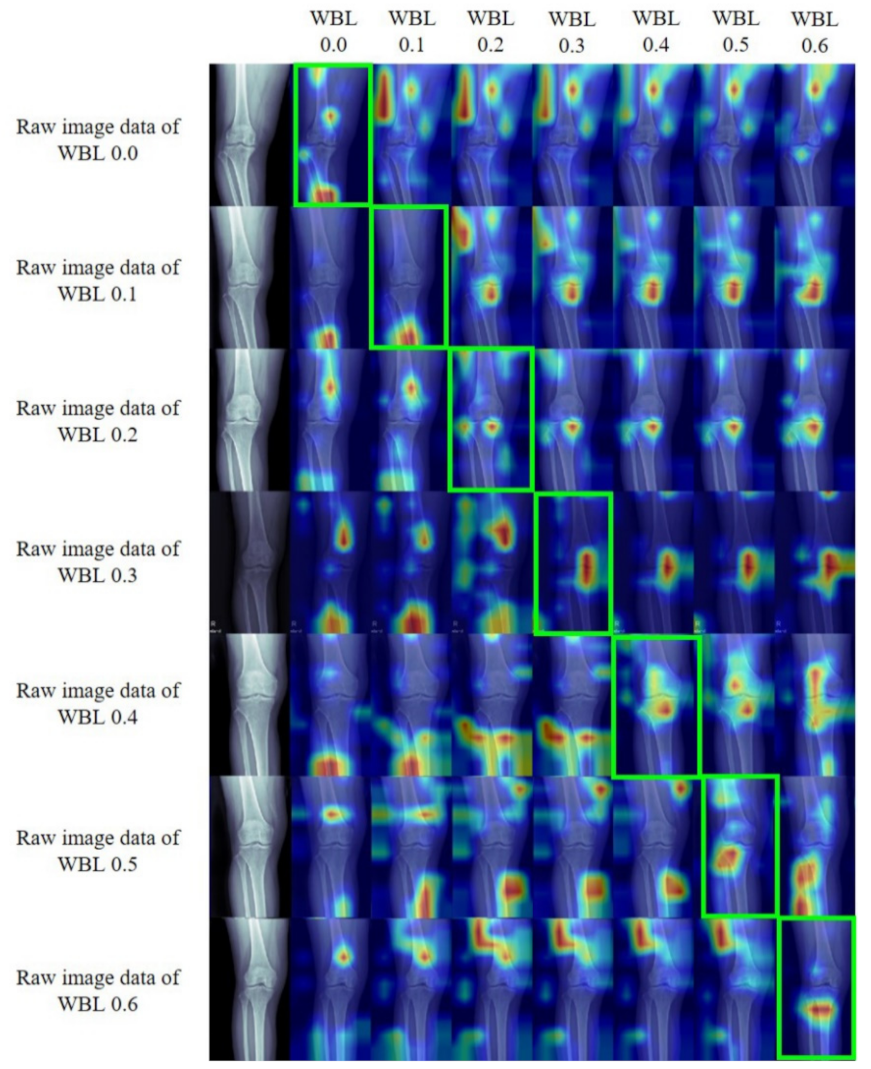

Gradient-Weighted Class Activation Mapping (Grad-CAM)